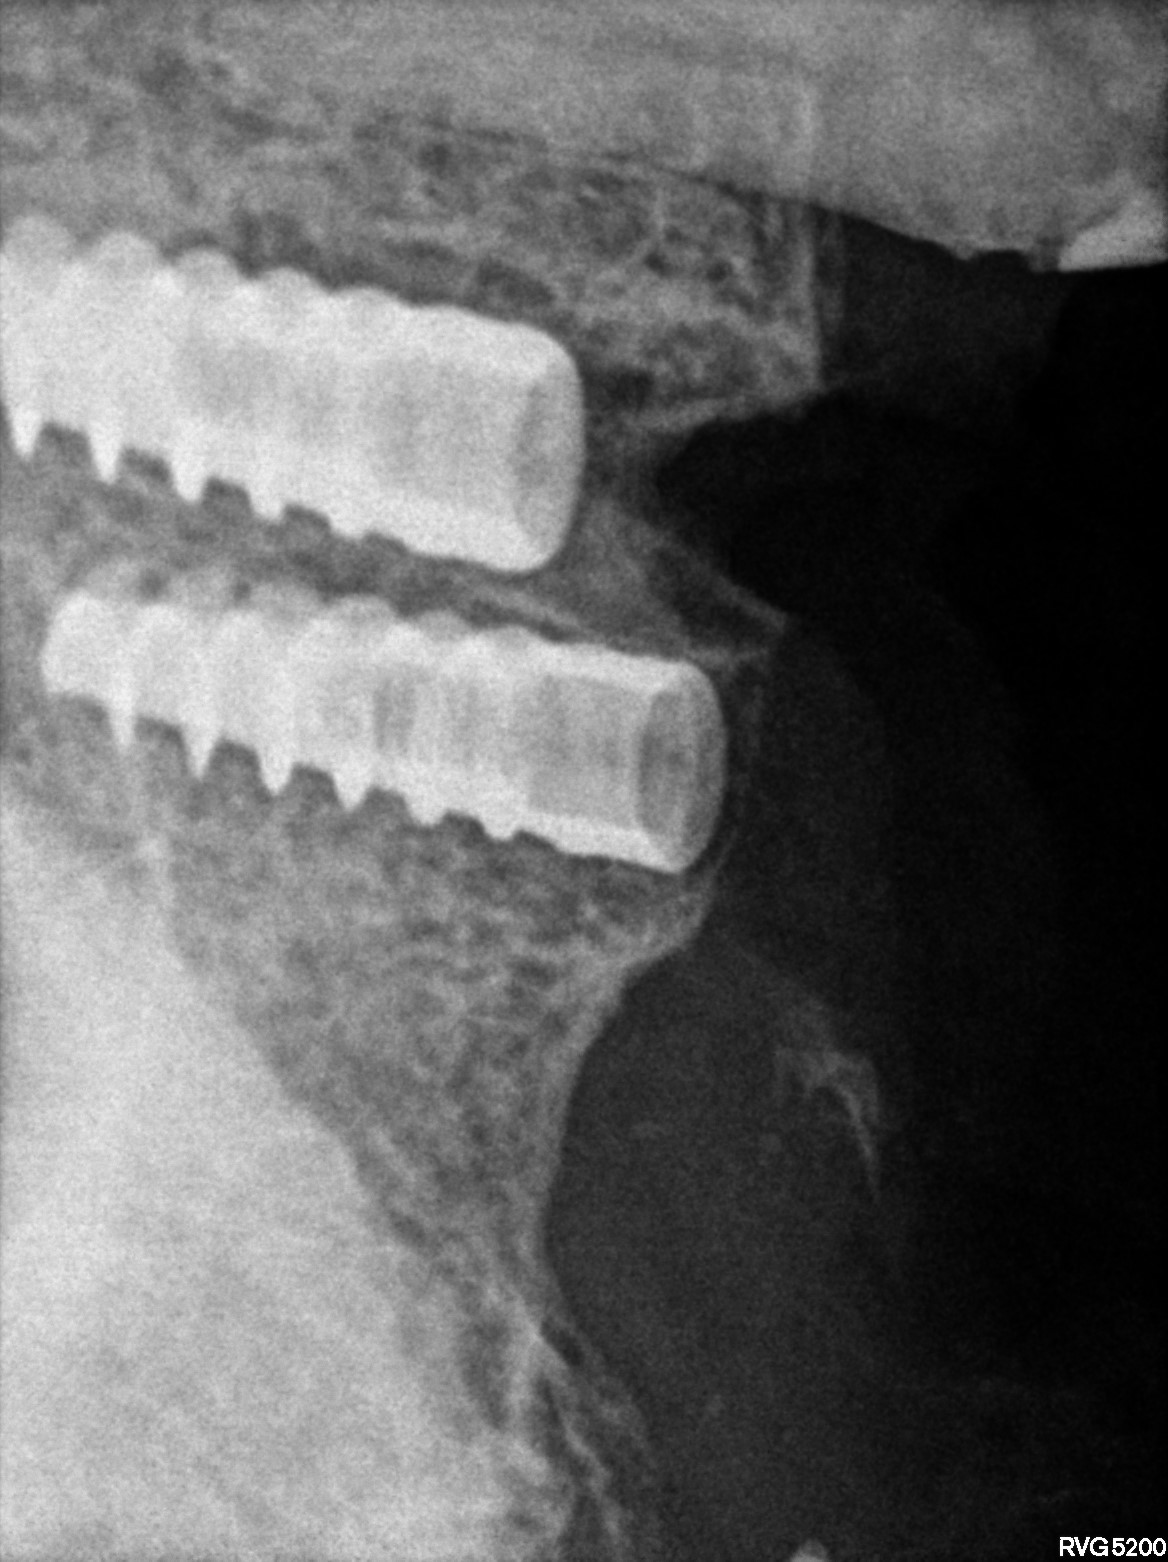

Dental Radiographs FHIR: DocumentReference · LOINC 24641-7

s.jpg

24641-7

R5.3.jpg